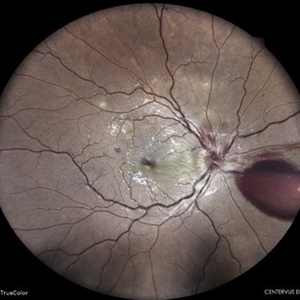

TRACTIONAL RETINAL DETACHMENT IN A CASE OF VASCULITIS

Mar 14 2022 by Akansha Sharma

MONTAGE OF A 27 YEAR OLD MALE WITH TREACTIONAL RETINAL DETACHMENT IN A CASE OF VASCULITIS

Photographer: Dr. Akansha Sharma-Retina Foundation, Ahmedabad

Condition/keywords: pan-retinal photocoagulation (PRP), tractional retinal detachment, VASCULITIS